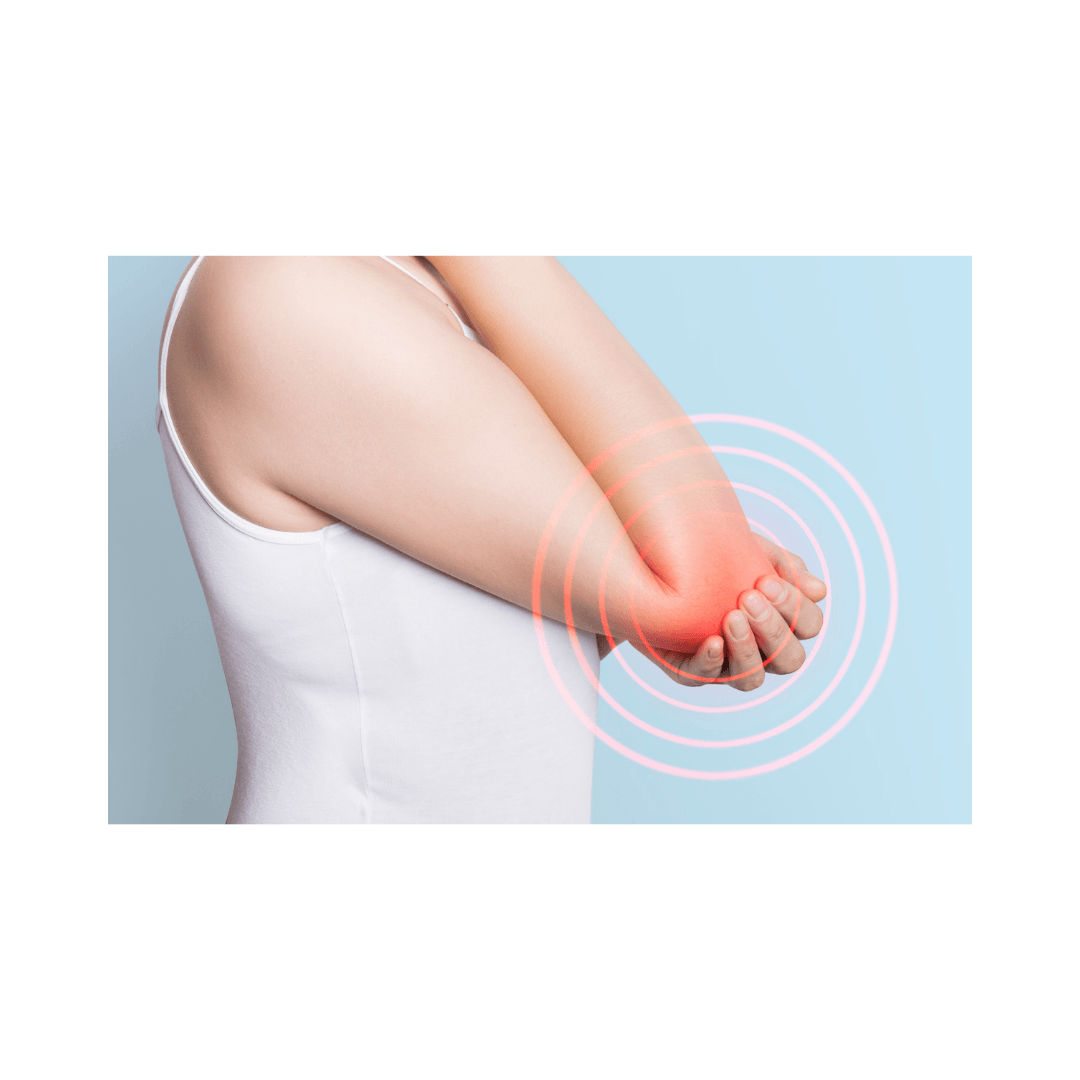

-Diagnóstico de atrapamientos o irritaciones nerviosas

- Mediante test neurodinámicos, se pueden identificar restricciones en la movilidad de un nervio, que pueden generar dolor, hormigueo, adormecimiento o debilidad.

- Ejemplo: Test de SLR para el nervio ciático o ULNT para el plexo braquial.

-Tratamiento del dolor neuropático

- La movilización neural ayuda a reducir la sensibilidad del sistema nervioso en casos de neuralgias, radiculopatías o síndromes de atrapamiento.

- Ejemplo: En el síndrome del túnel carpiano, se realizan deslizamientos del nervio mediano para mejorar su movilidad.